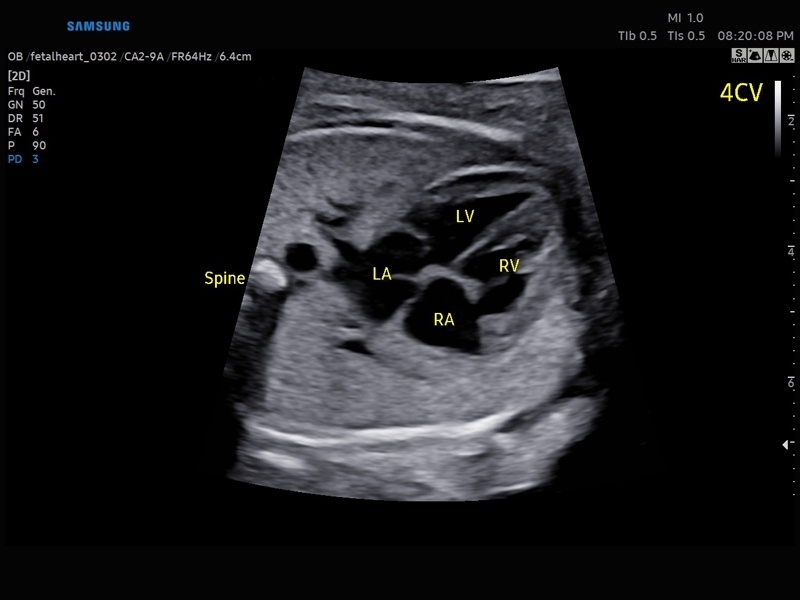

Ультразвуковой сканер V8-RUS является экспертным классом (премиальный уровень) и производится компанией Samsung Medison. Сканер V8 обеспечивает превосходное качество изображения благодаря использованию технологии Crystal Architecture™, которая включает в себя передовое аппаратное обеспечение, монокристальную технологию изготовления датчиков и сложную программную обработку ультразвуковых лучей.

Samsung Medison V8 представляет собой современную ультразвуковую систему, в которой воплощен многолетний опыт компании Samsung в создании эргономичного и интеллектуального диагностического оборудования. Система оснащена передовыми инструментами автоматизации, которые значительно упрощают рабочий процесс и повышают эффективность исследований.

• Акушерство и гинекология

• Кардиология